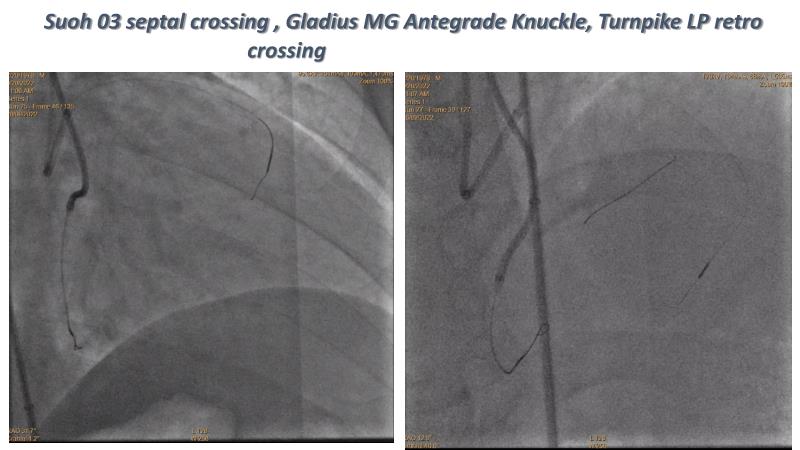

Thanks to the recorded complex CTO case shared in this session, learn how to perform ultra-low contrast PCI, learn what skills are required and tools available to perform ultra-low contrast coronary interventions in CTO, and become aware of the importance of relying on less contrast injections to guide PCI in complex CTO cases.

- To learn what are the skills required and tools available to perform ultra-low contrast coronary interventions in CTO

- To share and discuss a recorded complex CTO case showing how to perform ultra-low contrast PCI